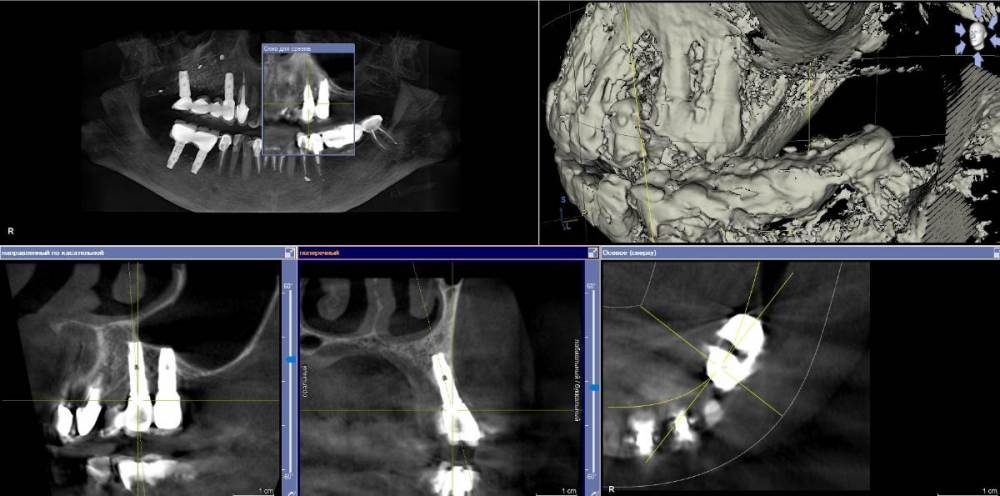

Ponchik Опубликовано 23 ноября, 2021 Поделиться Опубликовано 23 ноября, 2021 Заказ от начальства(ортопеда). Пациентка направлена ко мне со словами: вам сейчас косточки подсыпят, десенки пришьют и всё ок. Инересует второй сегмент, остальные и так ок. Работе всего пара лет. Делал не я. Импланты альфа-био. Прикреплёнки нет нигде. Всё хлюпает. Второй сегмент - я за удаление имплантов, через два месяца сунус+кость+мембрана(титан или полужесткая), через полгода 24, 26 импланты. Через 3 месяца мягкотканные дела, ещё через пару месяцев замаячит протезирование. (если всё остальное сложится) Как "подлепить" десну не снимая ортопедии, за два-три визита, хотя бы прикрыть витки? Я не знаю. Приму любой совет. Ссылка на комментарий

АнтонТЛТ Опубликовано 23 ноября, 2021 Поделиться Опубликовано 23 ноября, 2021 Витки заполировать и провести медикаментозную обработку. Но лучше конечно удалить такие имплантаты. Хорошо что в вашем случае нет зубов дистально) Ссылка на комментарий

АнтонТЛТ Опубликовано 23 ноября, 2021 Поделиться Опубликовано 23 ноября, 2021 А как там с небной стороны? Ссылка на комментарий

АнтонТЛТ Опубликовано 23 ноября, 2021 Поделиться Опубликовано 23 ноября, 2021 (изменено) Если небно тоже не очень, то добавить ещё разрез, отслоить и притянуть к имплантатам, чтобы более вертикально белый лоскут встал. Мезиально и дистально перемычки оставить для питания. Изменено 23 ноября, 2021 пользователем АнтонТЛТ Ссылка на комментарий

АнтонТЛТ Опубликовано 23 ноября, 2021 Поделиться Опубликовано 23 ноября, 2021 6 минут назад, Ponchik сказал: Пескоструй есть, буду им. Механическая и медикаментозная обработка это я представляю. Я с мягкими тканями не знаю что делать. И думаю A-oss (biooss жаба душит) какой добавить. По мягким тканям показал, что примерно нужно делать. Графт не нужно, не приживется. Он катит для кратерообразных дефектов. Ссылка на комментарий